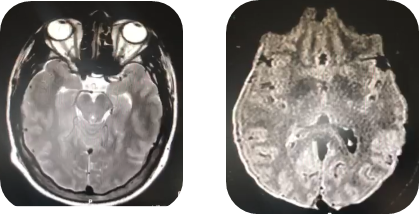

Simple cross-sectional tomography of the skull Figure-A, coronal section Figure-B, reports Fisher grade III subarachnoid hemorrhage, diffuse edema with displacement of the midline on the left side of up to 2.8 mm. Magnetic resonance imaging was performed on T2 and Flair sequences, which reported diffuse supratentorial cerebral edema, as well as the presence of Fisher grade III subarachnoid hemorrhage, predominantly on the right (Figure 2).

Figure 2 Magnetic Resonance of simple skull in T2 sequence, cross section..

Cross-sectional T2-weighted magnetic resonance imaging showing the presence of hemorrhage in the global supratentorial and tentorial subdural space, predominantly right. During the hospital stay in the infectious disease department (national medical center “La Raza”), his neurological status worsened, requiring advanced airway management. Therefore he was admitted to the Intensive Care Unit (ICU) for neurocritical monitorization and critcal care.